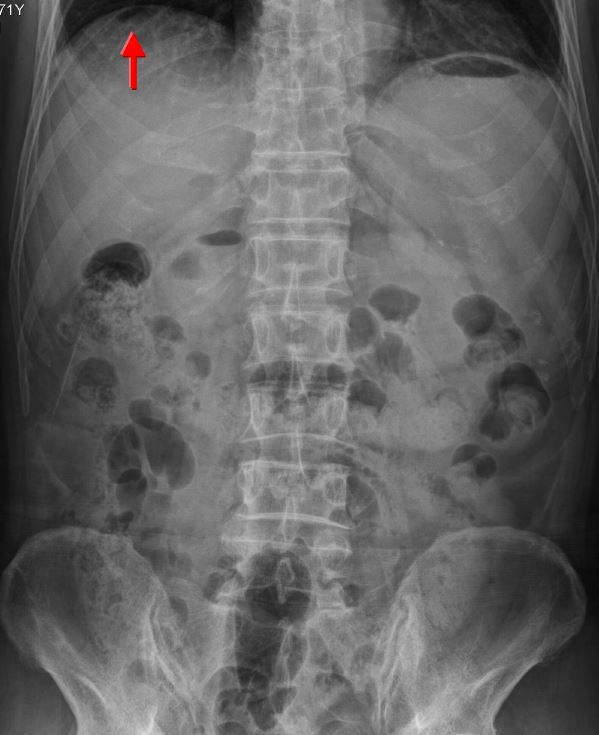

A. Sentinal loop due to acute pancreatitis

B. Small bowel obstruction

C. Regler’s sign due to GI perforation

D. Ascites with central floating gastrointestinal air